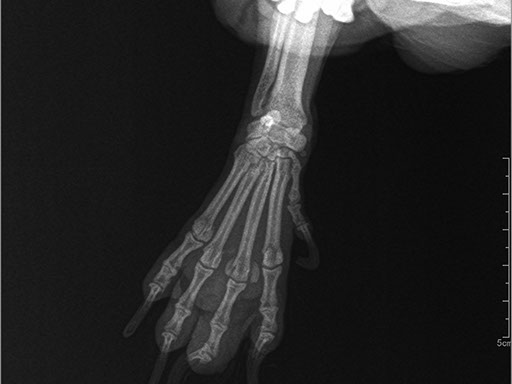

Коллиматорный прицел формирует пучок рентгеновского излучения на участок исследования. Проходя через ткани тела, излучение попадает на плоскопанельный цифровой детектор, который, в свою очередь, передает сигналы на компьютер.

В считанные секунды полученные данные обрабатываются компьютером посредством установленной на него программы визуализации, и сформированное клиническое изображение выводится на монитор лаборанта.

Клинические изображения (снимки) можно напечатать на принтере, сохранить в архиве или отправить по сети коллегам для оперативного консилиума.